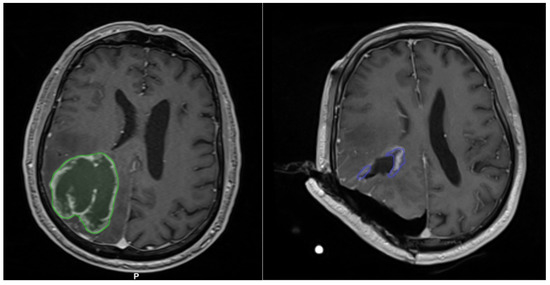

3.1.1. Case 1

3.1.2. Case 2